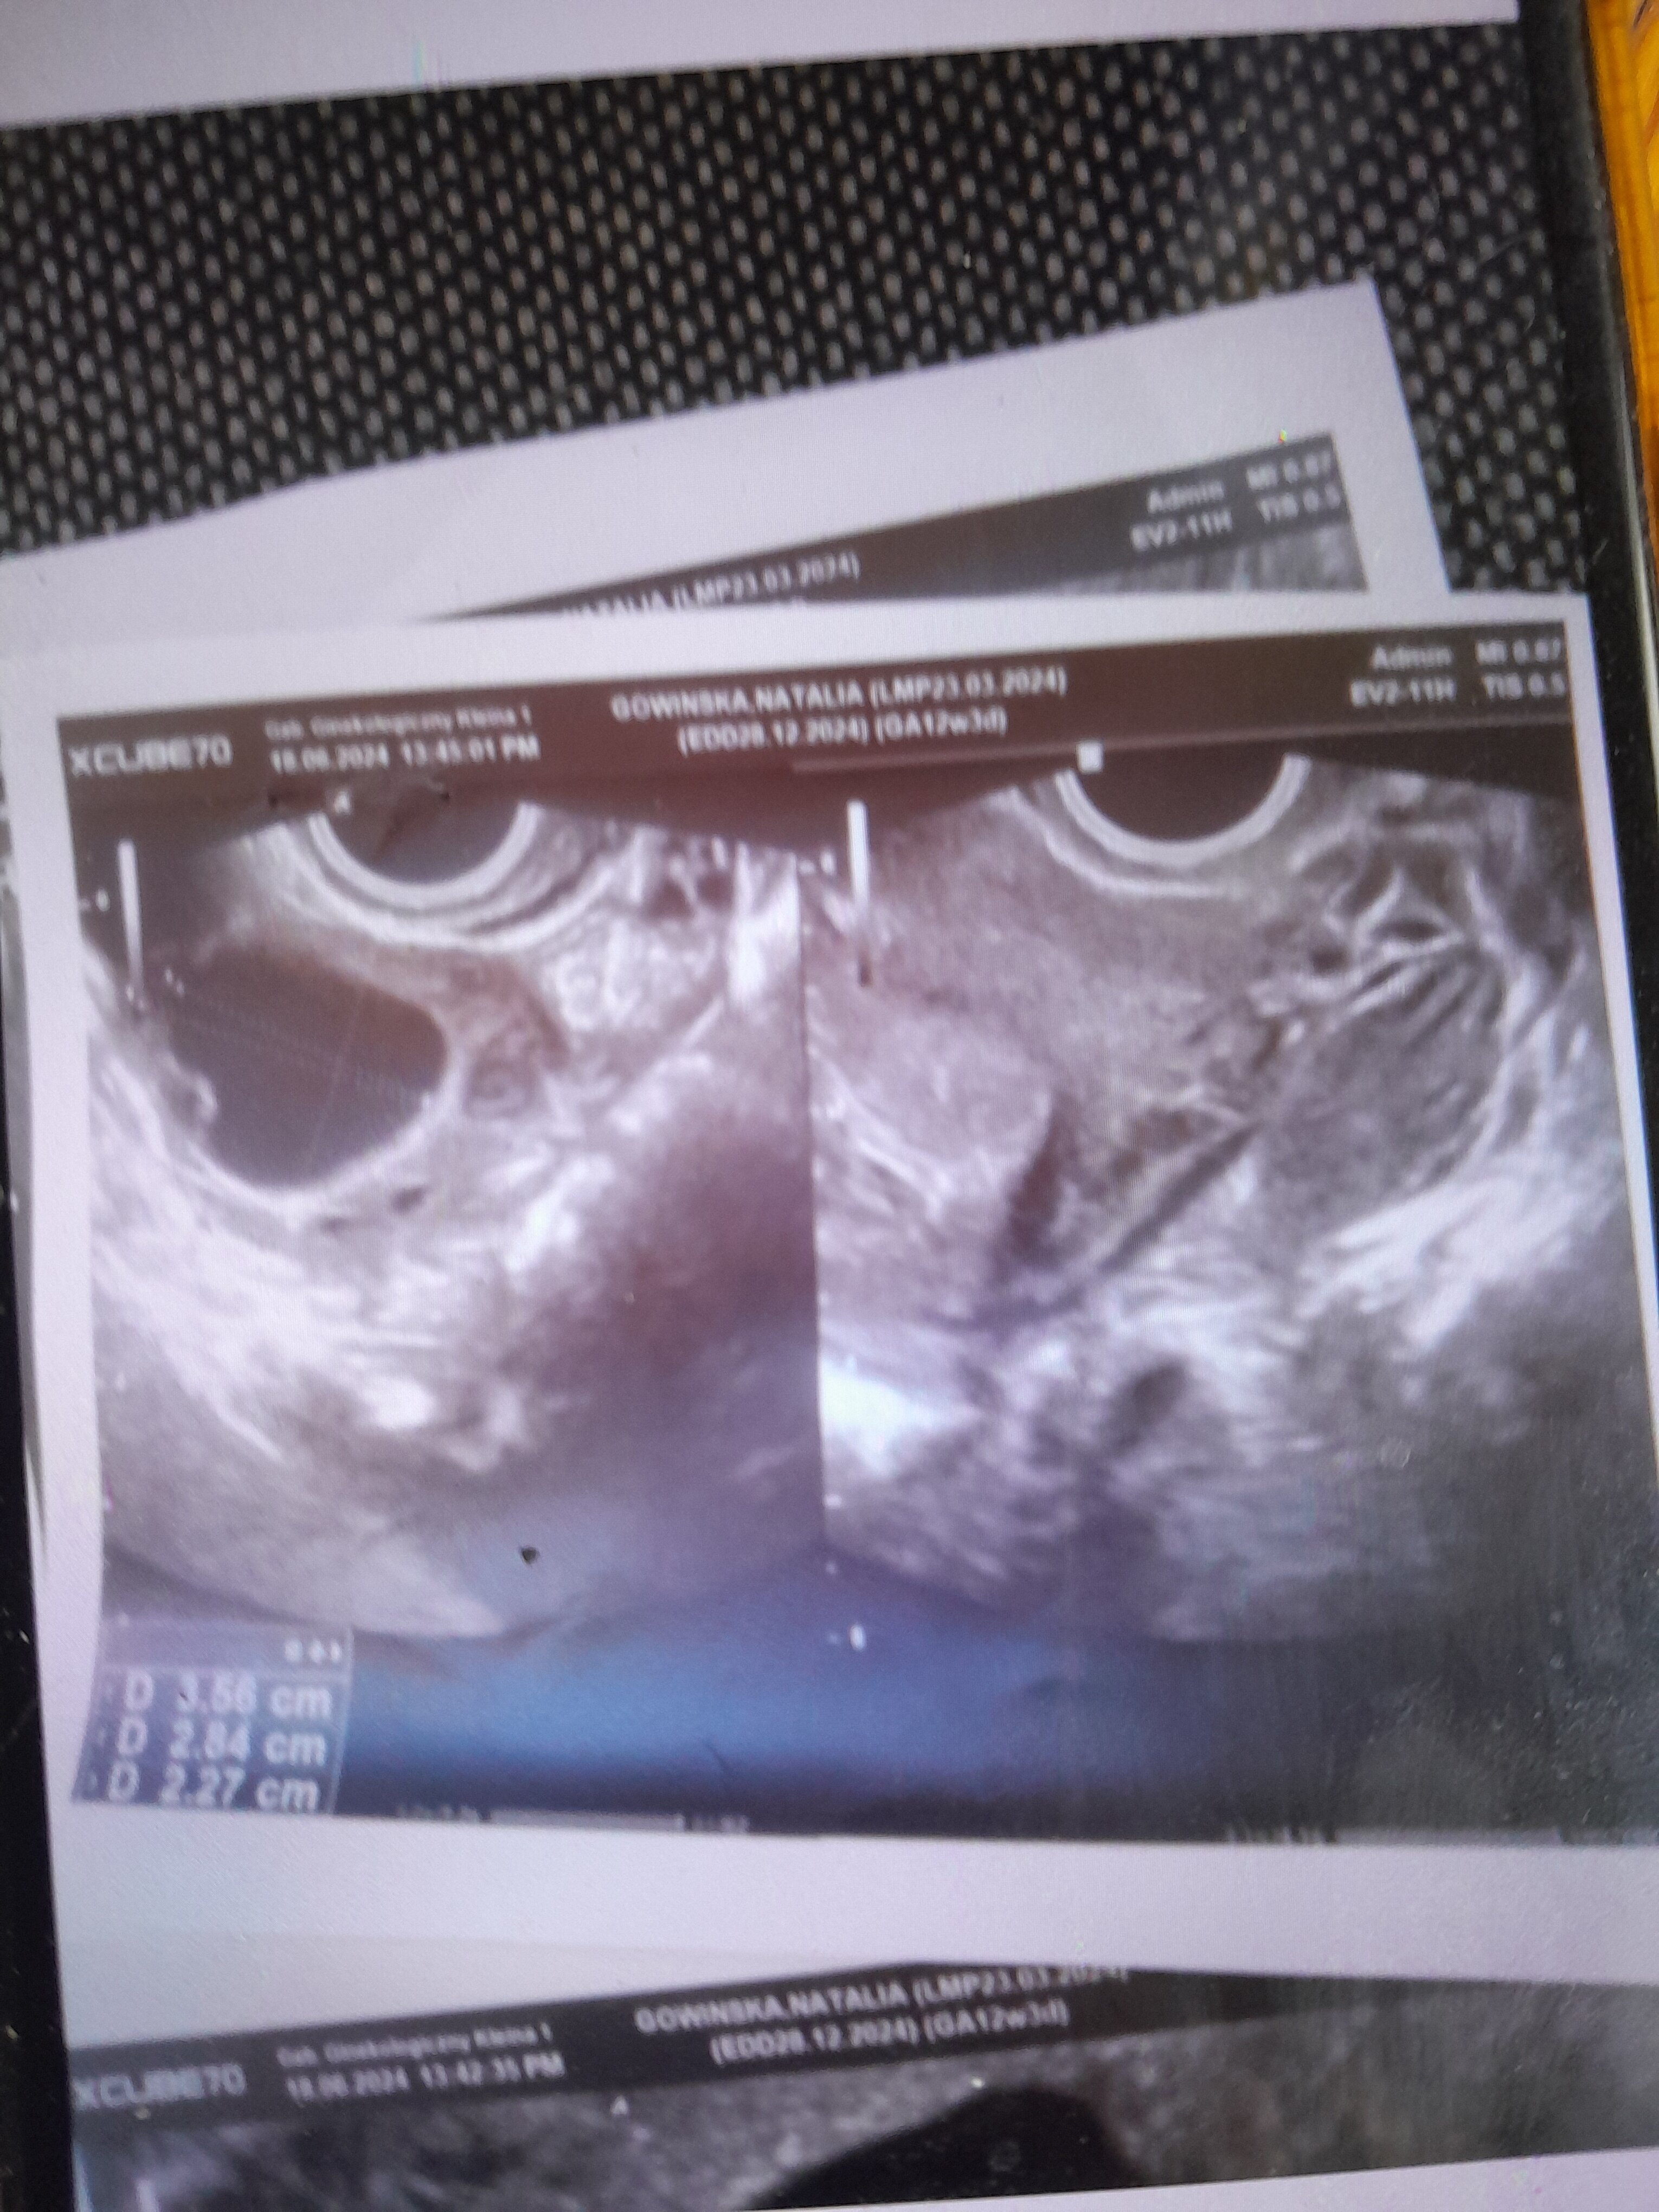

Dziś poszłam do obojętnie jakiego giną bo nad ranem krawilam .przerwzilam sie. Lekarz oznajmi mi że marnie to widzi. Jestem wg @ 5t4dz. Myślę że to chyba za wcześnie żeby tak określic żeby nie było już jakiś szans . Ale poczekam zrobię jutro ponownie betę. Dodam że jestem już po dwóch stratach. Uprosilam od niego zdjęcie USG .nie chciał mi dać bo jak to stwierdzil nic nie ma widać .. przesyłam wam załączniku zdjęcie . Idę do swojego lekarza w piątek bo wtedy przyjmuje i zobaczę czy coś sie zmieniło . Ps. Czy to mogą być dwa pęcherzyki ? Tego dzisiejszego sie nie pytałam bo źle zestresowałam jego zachowaniem .

Czy może być ciaza bliźniacze czy może jeden być większy a drugi pechezyk ciazowy czy może być 2